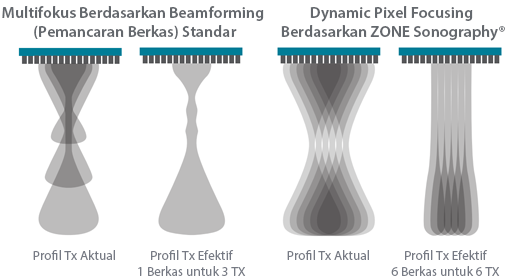

Sejak didirikan, Mindray terus mencari cara baru untuk meningkatkan keandalan diagnostik. Didukung Teknologi ZONE Sonography? terkini, platform ZST+ baru Resona 7 meningkatkan kualitas gambar ultrasound melalui pengambilan zona dan pemrosesan data saluran.